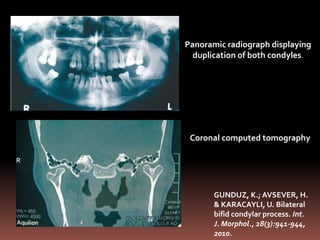

Panoramic radiograph displaying

duplication of both condyles.

Coronal computed tomography

GUNDUZ, K.; AVSEVER, H.

& KARACAYLI, U. Bilateral

bifid condylar process. Int.

J. Morphol., 28(3):941-944,

2010.